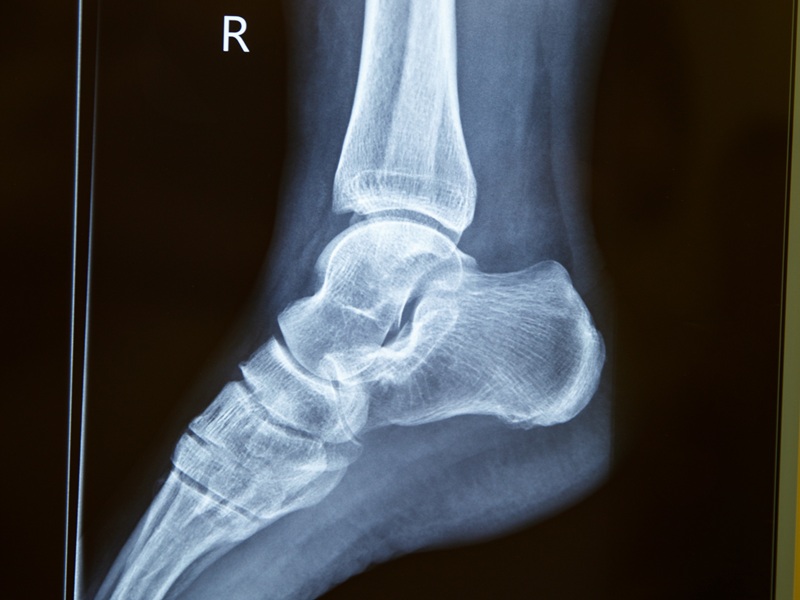

На відміну від рентгенографічного дослідження, за допомогою комп'ютерної томографії можна отримати тривимірне зображення гомілковостопного суглоба. Воно будується з окремих візуальних зрізів, які формуються під час покрокового сканування нижньої кінцівки. Знімки виходять більш точними і структури, зображені на них, можна розглядати за допомогою спеціальної програми на комп'ютері під різними кутами.

На знімках КТ гомілковостопного суглоба відображені таранна, велика та мала гомілкові кістки, навколишні м'які тканини. Можна виявити ознаки дегенеративних процесів, запалення, травм, новоутворення, що локалізуються у цій області.